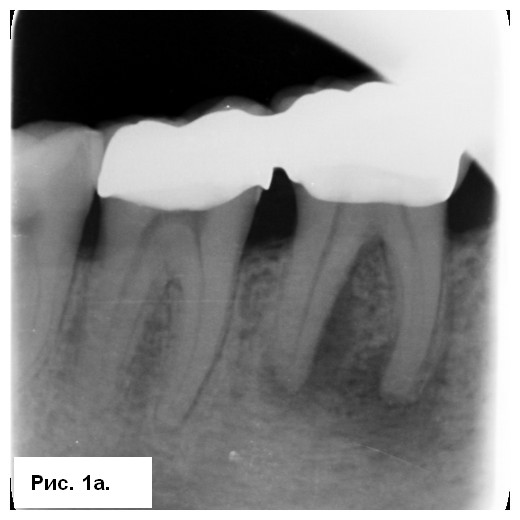

На рентгенограмме (рис. 1а) отмечались большие радиолюсцентые очаги на обоих корнях. Был поставлен диагноз: «некроз пульпы и острый апикальный абсцесс зуба 46». После консультации со стоматологом-ортопедом было принято решение провести эндодонтическое лечение с доступом к корневым каналам через существующую коронку. После вскрытия полости зуба было получено большое количество гнойного отделяемого с кровью (рис. 1b). Дренажу благоприятствовала ирригация 3 % NaOCl (рис. 1с), проведена инструментация корневых каналов системой 2Shape (MICRO-MEGA) и определена рабочая длина (рис. 2.а). Корневые каналы были заполнены гидроксидом кальция.

Симптоматика исчезла в последующие несколько дней. Второе посещение было проведено через 3 нед. Со слов пациента, зуб был асимптоматичным. После изоляции корневые каналы были вскрыты, проведена эвакуация гидроксида кальция. Затем каналы обтурировали биокерамическим силером BioRoot RCS (Septodont) методом одного штифта (рис. 2b) и выполнено композитное восстановление (рис. 2с). Была сделана послеоперационная радиография (рис. 3а), пациент записан на регулярные осмотры.